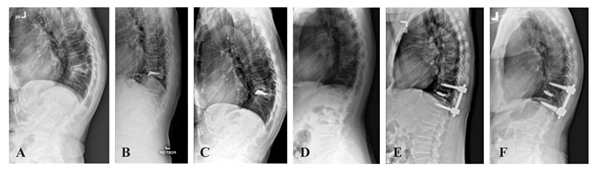

– ผลลัพธ์ทางรังสีวิทยา (Radiographic Outcomes): การจัดแนวกระดูกสันหลังในกลุ่มใส่สกรูยึดตรึงร่วมกับการฉีดซีเมนต์สามารถแก้ไขมุมโก่ง (Sagittal angle correction) ได้ดีกว่า

การรักษาผู้ป่วยกระดูกสันหลังหักจากโรคกระดูกพรุนด้วยวิธี ใส่สกรูยึดตรึงร่วมกับการฉีดซีเมนต์ให้ผลลัพธ์ในการจัดแนวกระดูกทางรังสีวิทยาและคุณภาพชีวิตของผู้ป่วยที่ดีกว่าการฉีดซีเมนต์ เพียงอย่างเดียวในระยะ 1 ปีหลังผ่าตัด แม้จะมีความเสี่ยงด้านการเสียเลือดและระยะเวลาการผ่าตัดที่เพิ่มขึ้น ทั้งนี้ ศัลยแพทย์จะพิจารณาวิธีการรักษาในแต่ผู้ป่วยแต่ละรายให้เหมาะสมโดยใช้ข้อมูลหลากหลายอย่าง นอกจากภาพรังสีวินิจฉัยเพียงอย่างเดียว